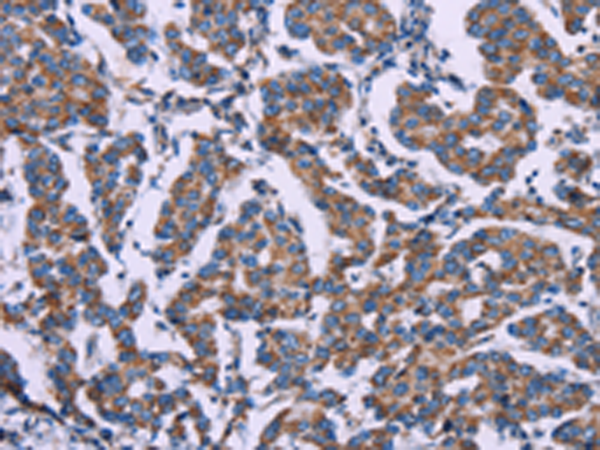

分类: 科研抗体货号: P07782别名:应用: IHC反应种属: Human, Mouse